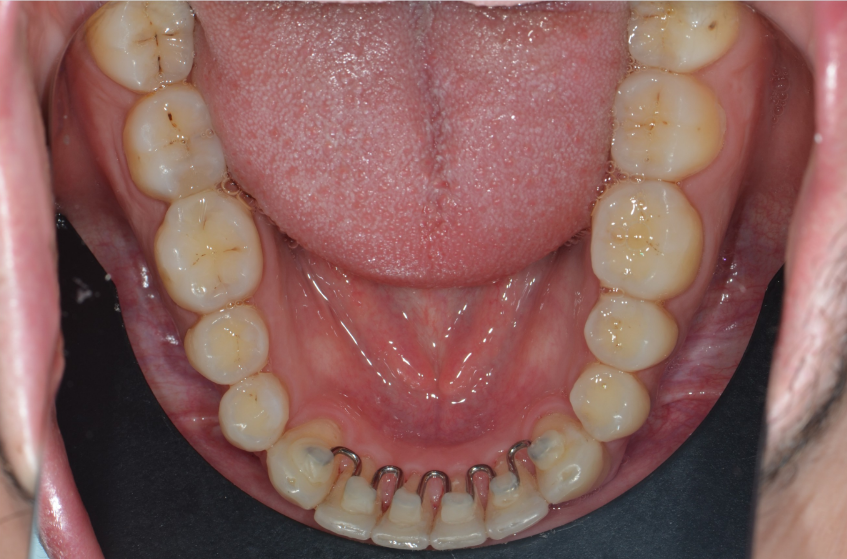

- Contenção Fixa: é um fio fino colado na parte de trás dos dentes, geralmente nos dentes inferiores da frente. A vantagem é que está sempre em ação, mas exige uma higienização mais cuidadosa.